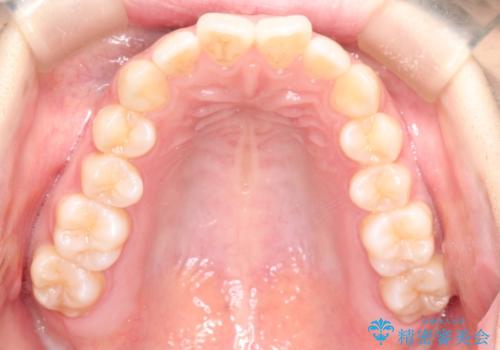

[ ディープバイト ] 深い噛み合わせの改善 マウスピース矯正

![[ ディープバイト ] 深い噛み合わせの改善 マウスピース矯正の症例 治療前](https://seimitsushinbi.jp/wp/wp-content/uploads/2022/03/dc9c092565b160bca6dd53d63f6aeffb-500x350.jpg?v=1646893459)

![[ ディープバイト ] 深い噛み合わせの改善 マウスピース矯正の症例 治療後](https://seimitsushinbi.jp/wp/wp-content/uploads/2022/03/5f1b12b750c3b8c04cdc49e53bc8f89d-500x350.jpg?v=1646893434)